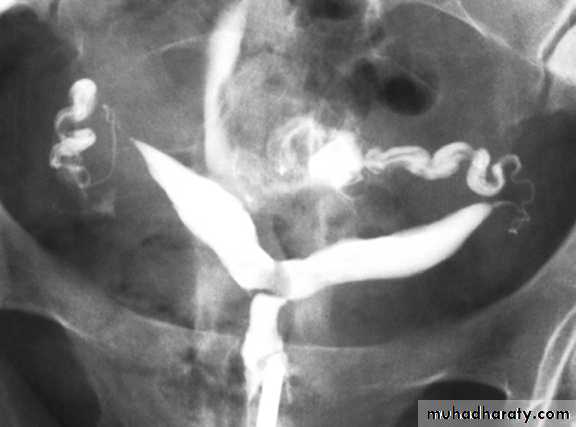

male &female reproductive tractsmammogram

genital tract and mammogram